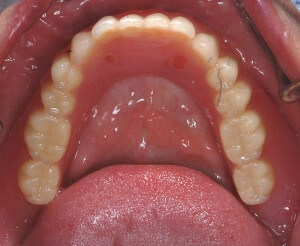

完成的下顎活動假牙會有兩個墊圈,利用兩個橡皮墊的力量幫助假牙穩定

DSC_3477